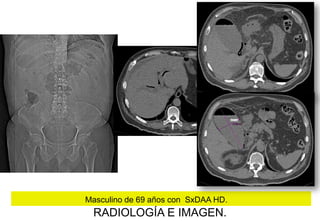

Masculino de 69 años con SxDAA HD.

RADIOLOGÍA E IMAGEN.